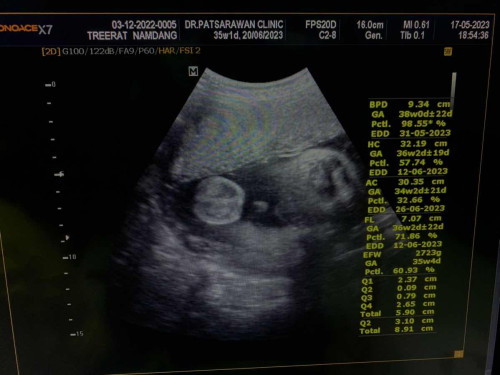

35w 2d แล้วครับเห็นแต่ไข่เลยเพราะท้องแม่แน่นไปหมด🤣 น้ำหนัก2,723กรัม หมอบอกคุณแม่ไม่จำเป็นต้องบำรุงอะไรมากแล้วนะคะเพราะตัวเล็กน้ำหนักเกินเกณฑ์ตลอด😂ตอนนี้กังวลมากค่ะว่าจะคลอดธรรมชาติไม่ไหว ใครพอจะมีวิธีคลอดง่ายๆมาแชร์บ้างมั้ยคะ💖